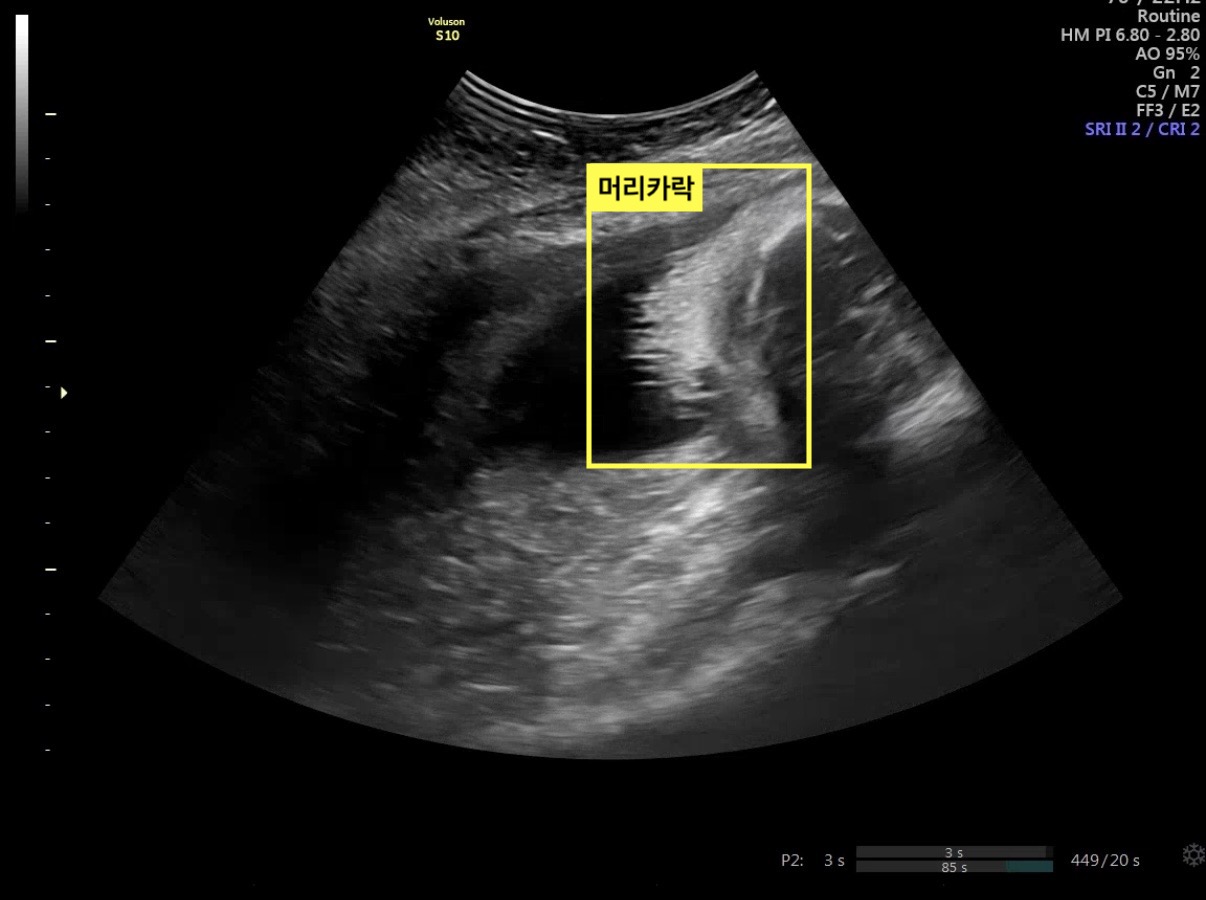

초음파 검사에서는 아기의 머리카락이

자라 있는 모습도 확인할 수 있었다.

임신 주수가 진행되면서 초음파로 관찰되는

아기의 모습이 이전과는 확연히 달려졌다는 점을

체감한 진료였다.